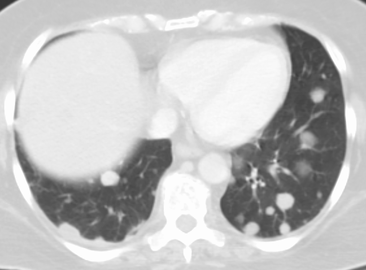

Pulmonary metastases shown on Chest X-Ray

The cells in a metastatic tumor resemble those in the primary tumor. Once the cancerous tissue is examined under a microscope to determine the cell type, a doctor can usually tell whether that type of cell is normally found in the part of the body from which the tissue sample was taken.

For instance, breast cancer cells look the same whether they are found in the breast or have spread to another part of the body. So, if a tissue sample taken from a tumor in the lung contains cells that look like breast cells, the doctor determines that the lung tumor is a secondary tumor. Still, the determination of the primary tumor can often be very difficult, and the pathologist may have to use several adjuvant techniques, such as immunohistochemistry, FISH (fluorescent in situ hybridization), and others. Despite the use of techniques, in some cases the primary tumor remains unidentified.